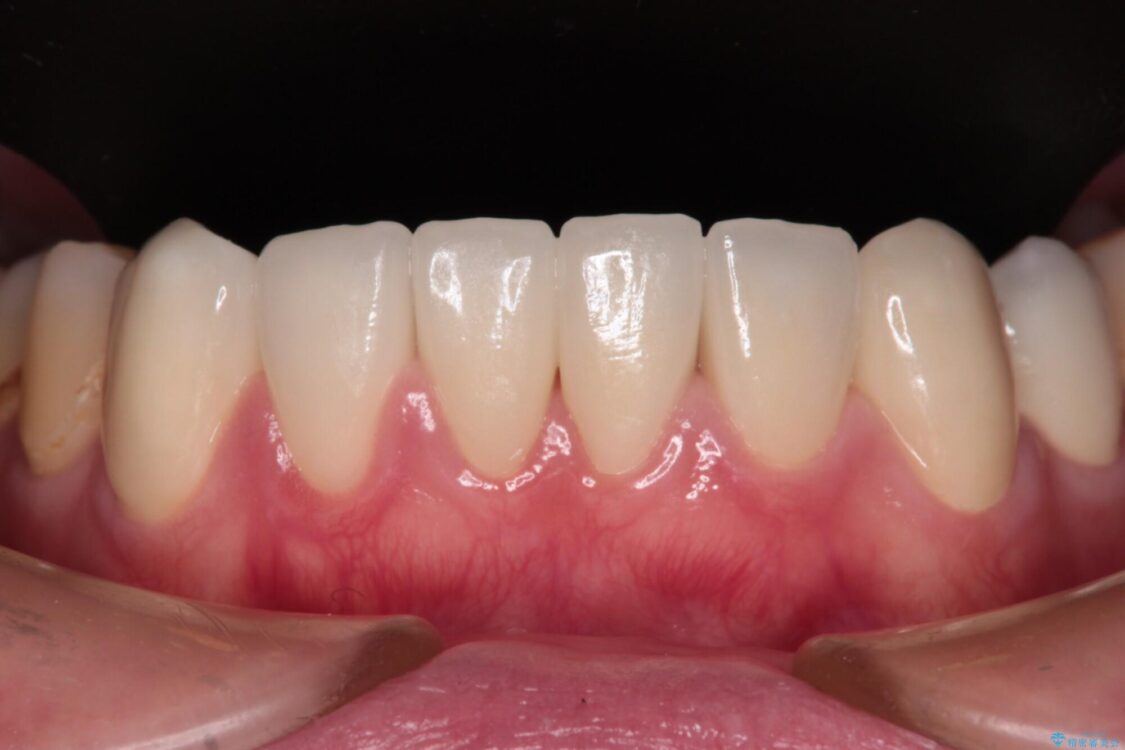

治療後について

歯肉移植術による根面被覆を行うかどうかは非常に悩まれていましたが、歯肉が覆われたことで長く見えていた歯の長さが整い、きれいな前歯の仕上がりとなりました。

治療後

• むし歯だらけの前歯をオールセラミッククラウンできれいに 治療後画像